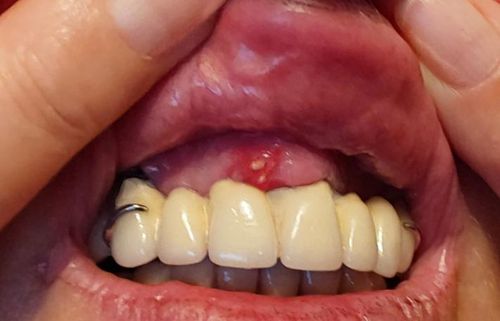

Bei Aphthen handelt es sich um häufig auftretende, schmerzhafte Schädigungen der Schleimhaut, die von einem entzündlichen Randsaum umgeben sind. Aphthen erscheinen meist gehäuft als weiß-rötliche, entzündete Stellen an der Mundschleimhaut. Aphthen treten meist wiederkehrend auf.

Aphthen erscheinen meist als kleine, rundlich, weiße Stellen an der Innenseite der Lippe oder Wangen. Zunge oder Gaumen sind eher selten betroffen.

Aphten sind leicht eingesunken und haben einen rötlichen Rand.